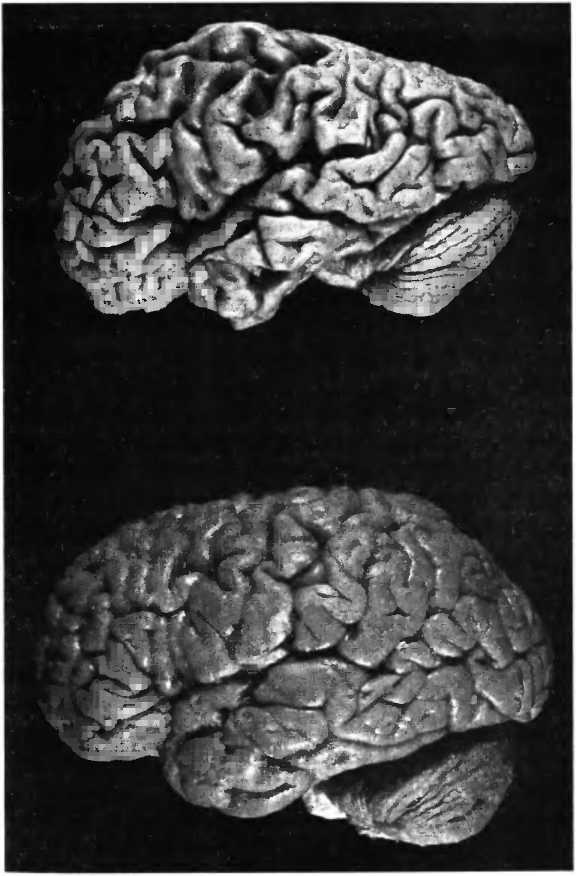

Несмотря на часто сильное сморщивание мозга при болезни Альцгеймера (рис. 31), так что он становится похож на грецкий орех, общее число нейронов в его структуре не уменьшается. Вопреки распространенному мнению, массовой гибели нервных клеток во всем мозге не происходит. Смерть клеток ограничивается пределами нескольких областей мозга: энторинальной коры, части гиппокампа и голубого пятна (locus coeruleus) — и наступает довольно поздно, тогда как снижение активности и поэтому сморщивание нервных клеток (рис. 32) можно наблюдать по всему мозгу уже на ранних стадиях болезни. Этим объясняется тот факт, что в начале болезни ее симптомы могут быть подвержены значительным колебаниям. В какой-то момент у человека могут резко проявиться симптомы деменции, но после этого он вновь оказывается в состоянии поддерживать разговор на обычном уровне. Если бы причиной нарушений памяти на ранней стадии болезни действительно являлась смерть клеток, то никакие колебания симптоматики не возникали бы. Смерть клетки необратима. Еще до того как возникают первые нарушения памяти, измерения показывают уменьшение в мозге глюкозообмена. Внутривенное вливание глюкозы или инсулина улучшает когнитивные способности и указывает на то, что нарушение обмена веществ в мозге является фактором, ограничивающим функциональные способности пациентов.

Рис. 31. При болезни Альцгеймера часто наблюдается сильное сморщивание (атрофия) мозга, он становится похож на грецкий орех. Внизу — здоровый мозг.